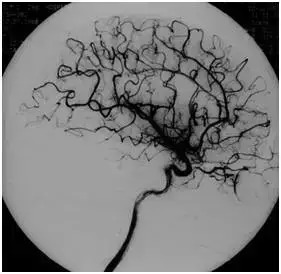

中国DSA技术:

1989年,万东医疗研发生产的中国首台DSA入驻北京军区总医院

▲ 中国第一台自主研发的DSA